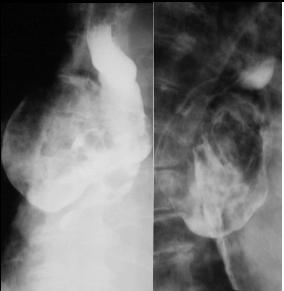

A etat tardive oesophage dilate et

alonge en forme de petit chaussette . |

Megaoesophage en face

et en profile OAD |